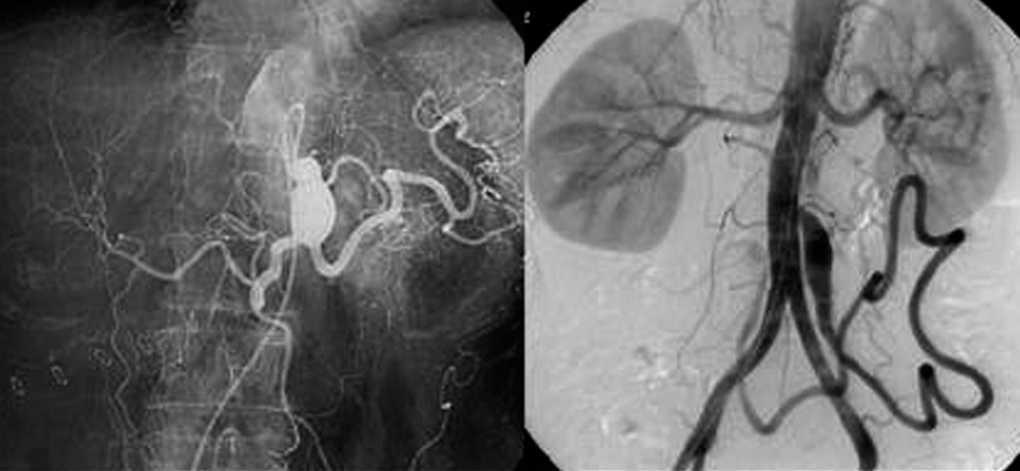

Ocho aneurismas (en 6 pacientes) no fueron tratados. Dos pacientes fallecieron poco después del diagnóstico de 2 aneurismas del TC (fig. 1). Uno de ellos por rotura de un aneurisma de aorta torácica por lo que se realizó un escáner que diagnosticó el aneurisma de TC. El otro falleció por una complicación de una fístula arteriovenosa pulmonar en el contexto de una enfermedad de Rendu-Osler. Otros dos no fueron tratados por alto riesgo quirúrgico; uno presentaba un aneurisma de AE y el otro aneurismas de TC, AE y AH. El primero era un paciente varón de 64 años con un hiperaldosteronismo de etiología desconocida, hipertenso, con miocardiopatía hipertensiva severa y bronconeumopatía obstructiva crónica severa que presentaba un aneurisma de AE de 1,2 cm de diámetro calcificado que se decidió no tratar; 6 años después del diagnóstico el aneurisma no ha sufrido ninguna variación. El segundo paciente, de 81 años, fue diagnosticado a raíz del estudio de una anemia severa, de aneurismas de TC, AE y AH; no fue tratado debido al mal estado general, la edad avanzada y la afección cardíaca y pulmonar asociada.

Fig. 1. Aneurisma de tronco celíaco (izquierda); aneurisma de mesentérica inferior (derecha).

El caso del aneurisma de MI se reparó mediante la resección del segmento aneurismático y el reimplante de la arteria en la aorta (fig. 1).